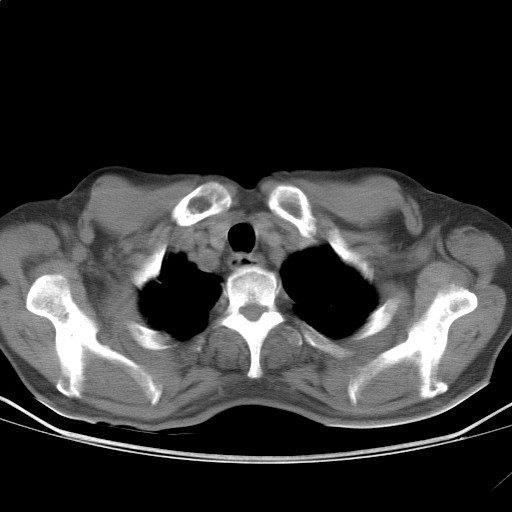

以下是引用随光逐影在2009-5-1 13:53:00的发言:[br]考虑为:1)两肺血行播散型肺结核;2)右肺下叶炎症感染。3)右侧胸膜增厚。